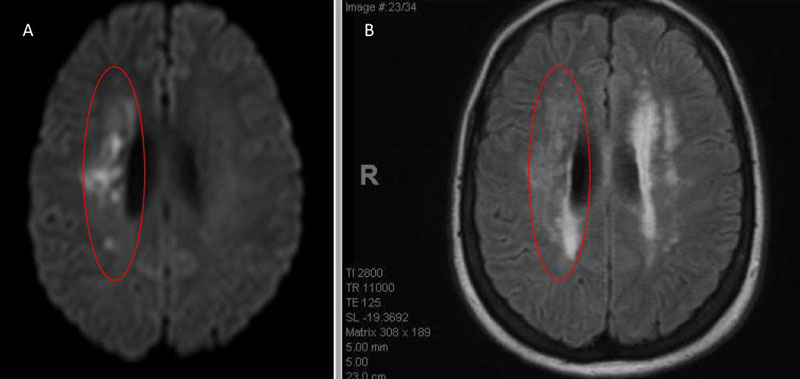

Catheter cerebral angiography was then performed which demonstrated the 99% stenosis with distal vascular collapse and extension of the plaque superiorly into the mid third of the cervical right ICA (Figure 4). Interrogation for collaterals from the left ICA and posterior circulations demonstrated very small and minimal contributions from the anterior communicating artery and posterior communicating artery of the Circle of Willis.

Figure 4. A) DS Angiogram demonstrates severity and extent of plaque to C2-3 level (blue). B) And marked delay of ICA perfusion (yellow) relative to ECA branches (green).